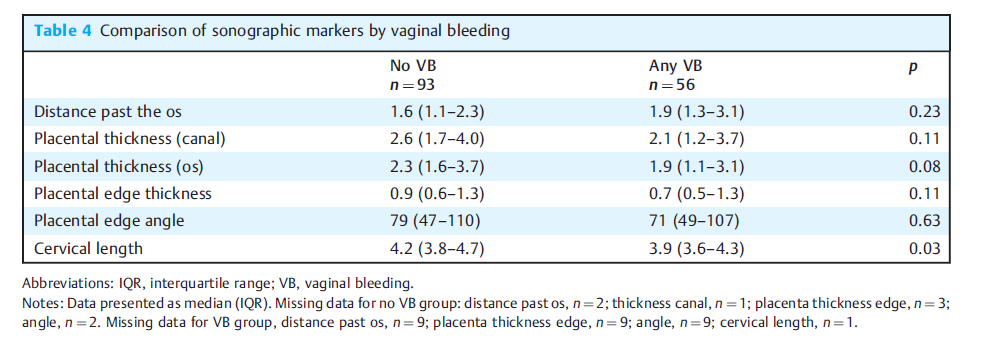

在单因素分析中,VB患者的CL降低(3.9 vs 4.2 cm;P < 0.01),见下表。